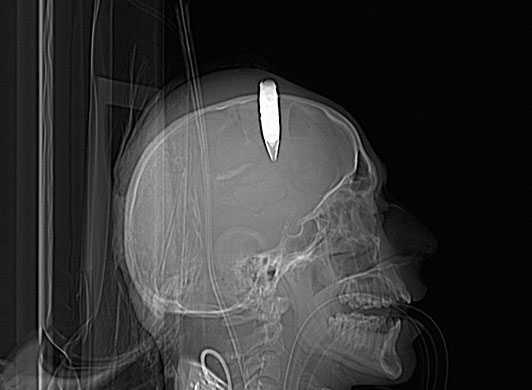

24 Hours in Pics: An incendiary round is removed from an Afghan National Army soldier

Bagram, Afghanistan: A Cat scan shows a 14.5mm incendiary round removed from the scalp of an Afghan soldier at Craig Joint Theater hospital

Photograph: AP